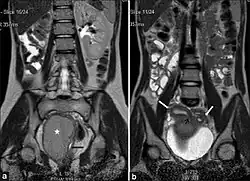

| (a) Coronal Single shot T2W image shows absence of the right kidney. The distended hemivagina (asterisk) is seen on the right side and the normal collapsed left hemivagina with minimal fluid is seen adjacent to it (black arrow). The distended hemivagina ends above the introitus and its contents are hypointense to fat. (b) Coronal Single shot T2W image shows right and left uterine horns (white arrows). The right uterine horn cavity is seen to communicate with the upper end of the fluid collection in right hemivagina (small black arrow). |